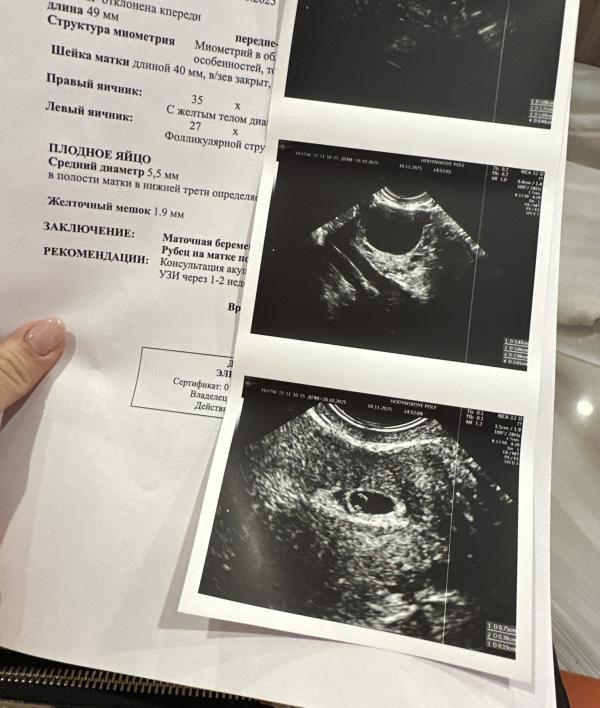

А вот и наше первое узи) уместился в домике ) 😍теперь ждём следующее, чтобы послушать сердечко, через две недели🙏🏻

Плакала так. Чудо мое 🙏🏻🥹